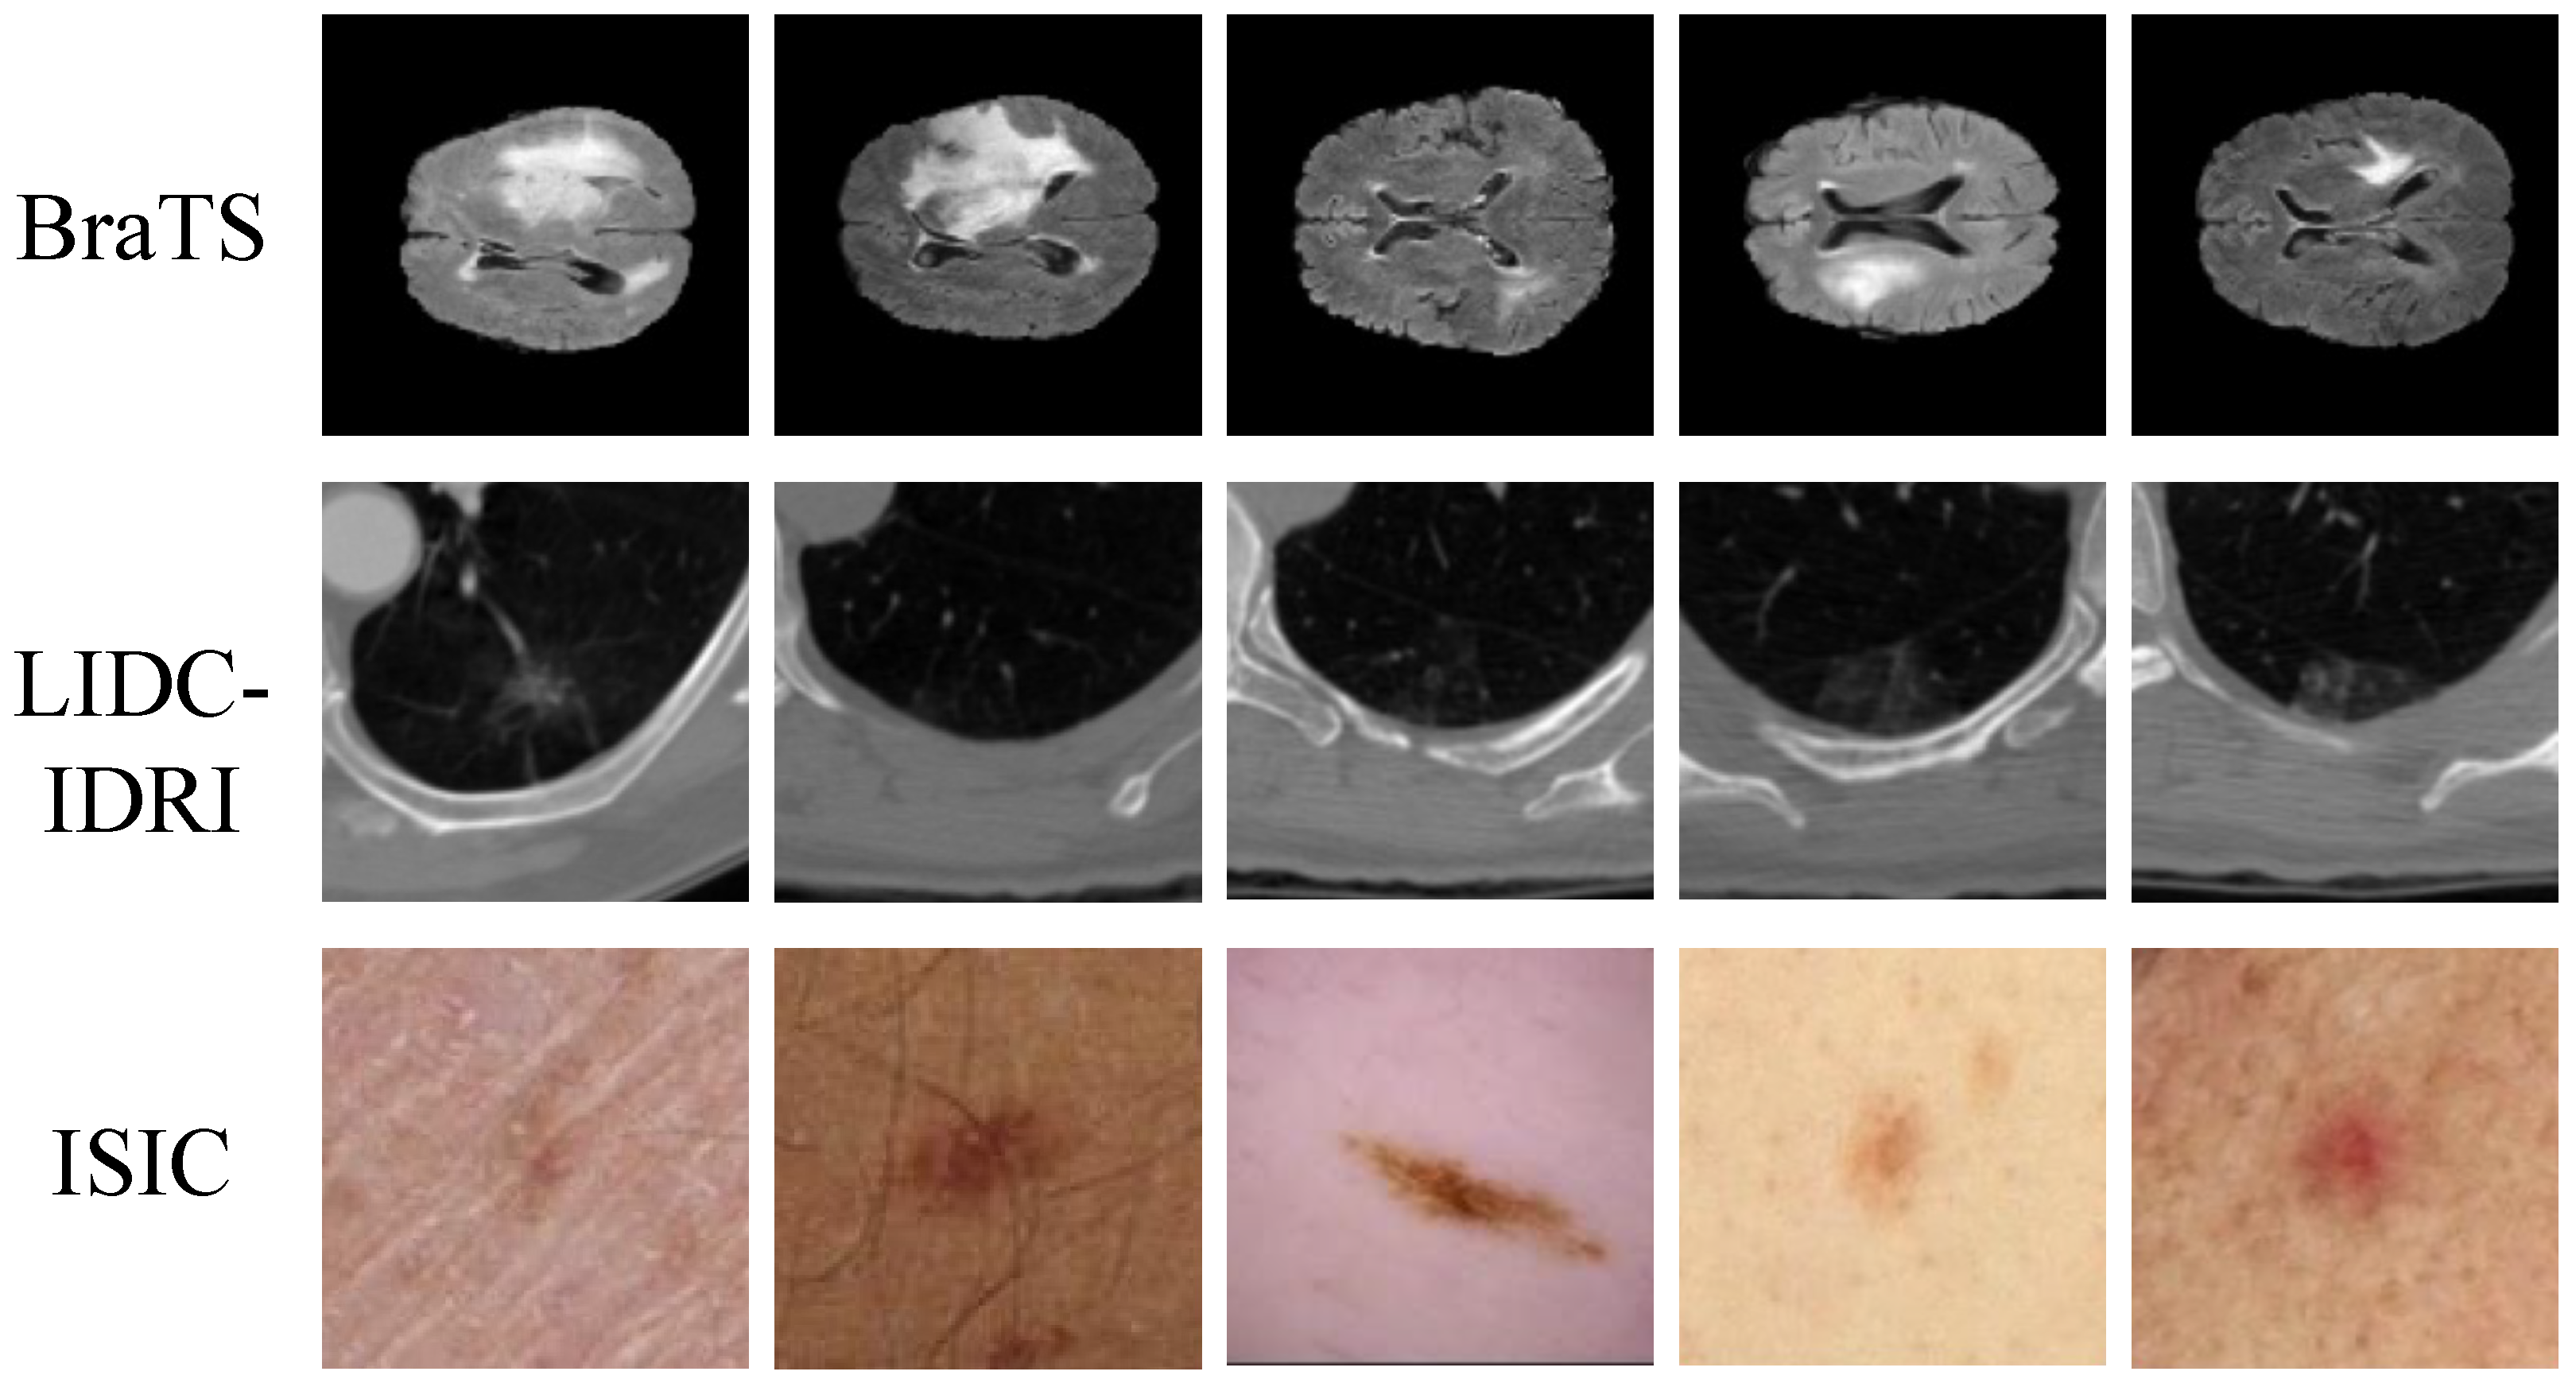

The collection and construction of medical imaging datasets served as a fundamental basis for this study. To ensure the effectiveness and generalization ability of the proposed framework across multi-modal, multi-disease, and multi-scale scenarios, both publicly available and self-collected medical imaging datasets were employed, as shown in Table 1 and Figure 1. The public datasets included the Brain Tumor Segmentation Challenge dataset (BraTS) [48], the Lung Image Database Consortium and Image Database Resource Initiative (LIDC-IDRI) [49], and the International Skin Imaging Collaboration (ISIC) dataset [50]. The BraTS dataset comprises multi-center (MRI) scans collected between 2015 and 2021. It contains four imaging modalities (T1, T1CE, T2, and FLAIR), and each case is accompanied by expert annotations of tumor regions. The spatial resolution is standardized to , and the primary characteristic lies in its ability to capture multi-modal structural information of brain tumors. The LIDC-IDRI dataset was collected by multiple institutions in North America from 2004 to 2008, primarily consisting of low-dose helical CT scans of the chest. Each case was independently annotated by four radiologists, featuring substantial variation in nodule diameters, blurred boundaries, and diverse morphologies, making it well-suited for small-scale lesion recognition and segmentation. The ISIC dataset includes dermoscopic images collected across Europe and North America between 2016 and 2020. Images were obtained using high-resolution digital dermatoscopes and cover a wide range of conditions such as melanoma, keratosis, and benign nevi. The resolution ranges from to , and the dataset is characterized by pronounced color variations and complex backgrounds. This study was approved by the Biomedical Research Ethics Committee (Approval number IRB00001052-25150, dated 23 January 2025).

Figure 1.

Samples of medical imaging datasets used in this study.